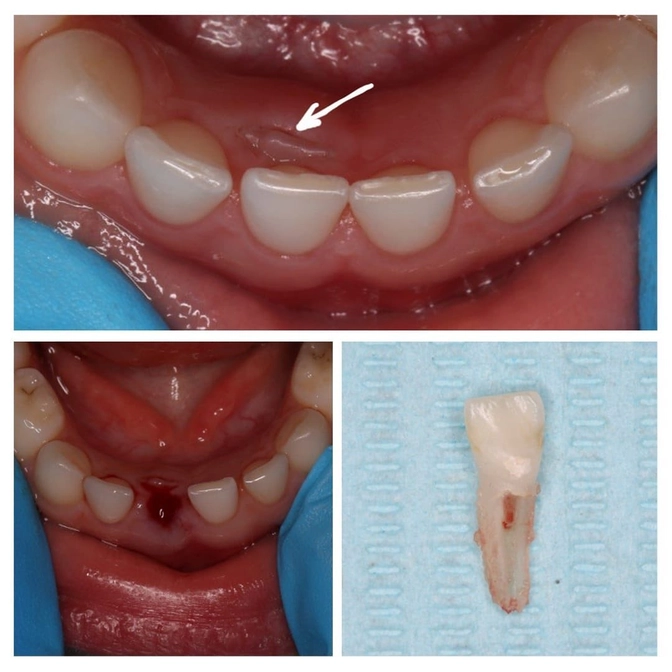

Этой пациентке 5 лет.

Её принимала детский стоматолог Мария Штельмах.

Нижний молочный резец был слобо подвижен, а постоянный уже прорезался вне зубного ряда.

Теперь проблема решена — молочный резец удален.

Постоянный через некоторое время должн занять свое место.

А если нет, то нужно будет обратиться к ортодонту.